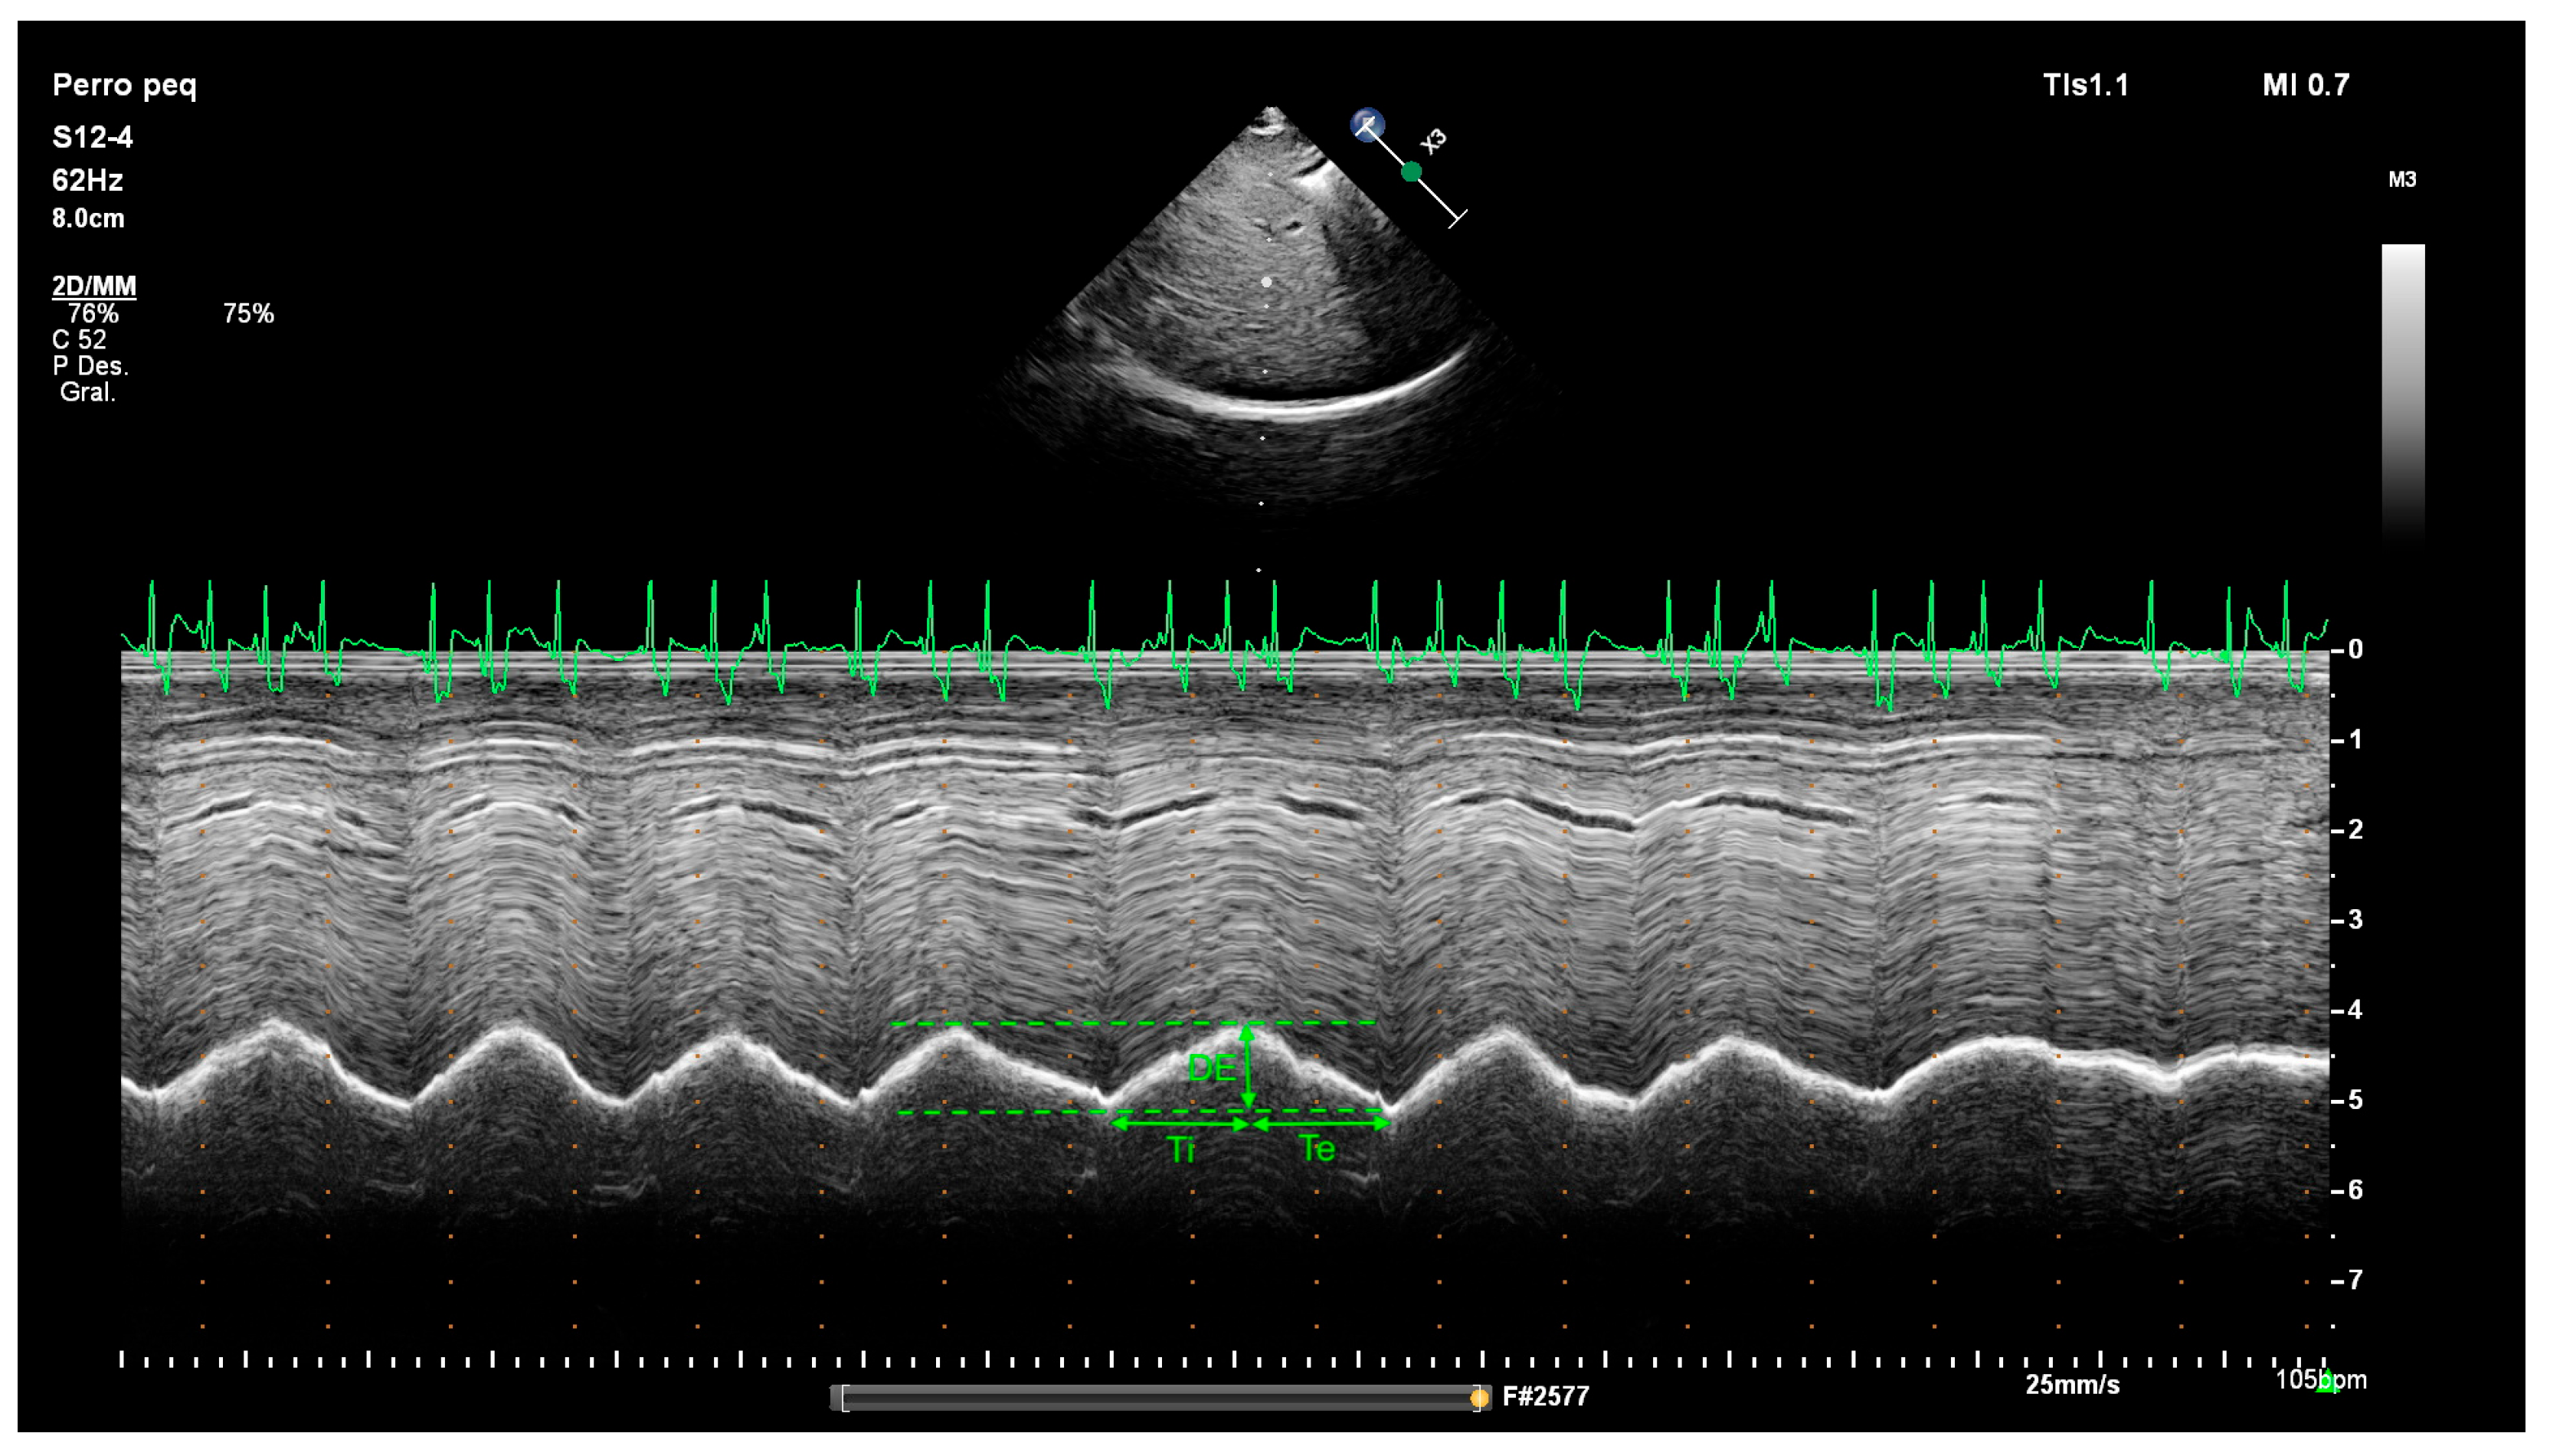

2.2. Diaphragm Ultrasound Technique and Diaphragmatic Measurements

| DE | Diaphragmatic excursion |

| Te | Expiratory time |

| Ti | Inspiratory time |

| Ve | Diaphragmatic contraction velocity |